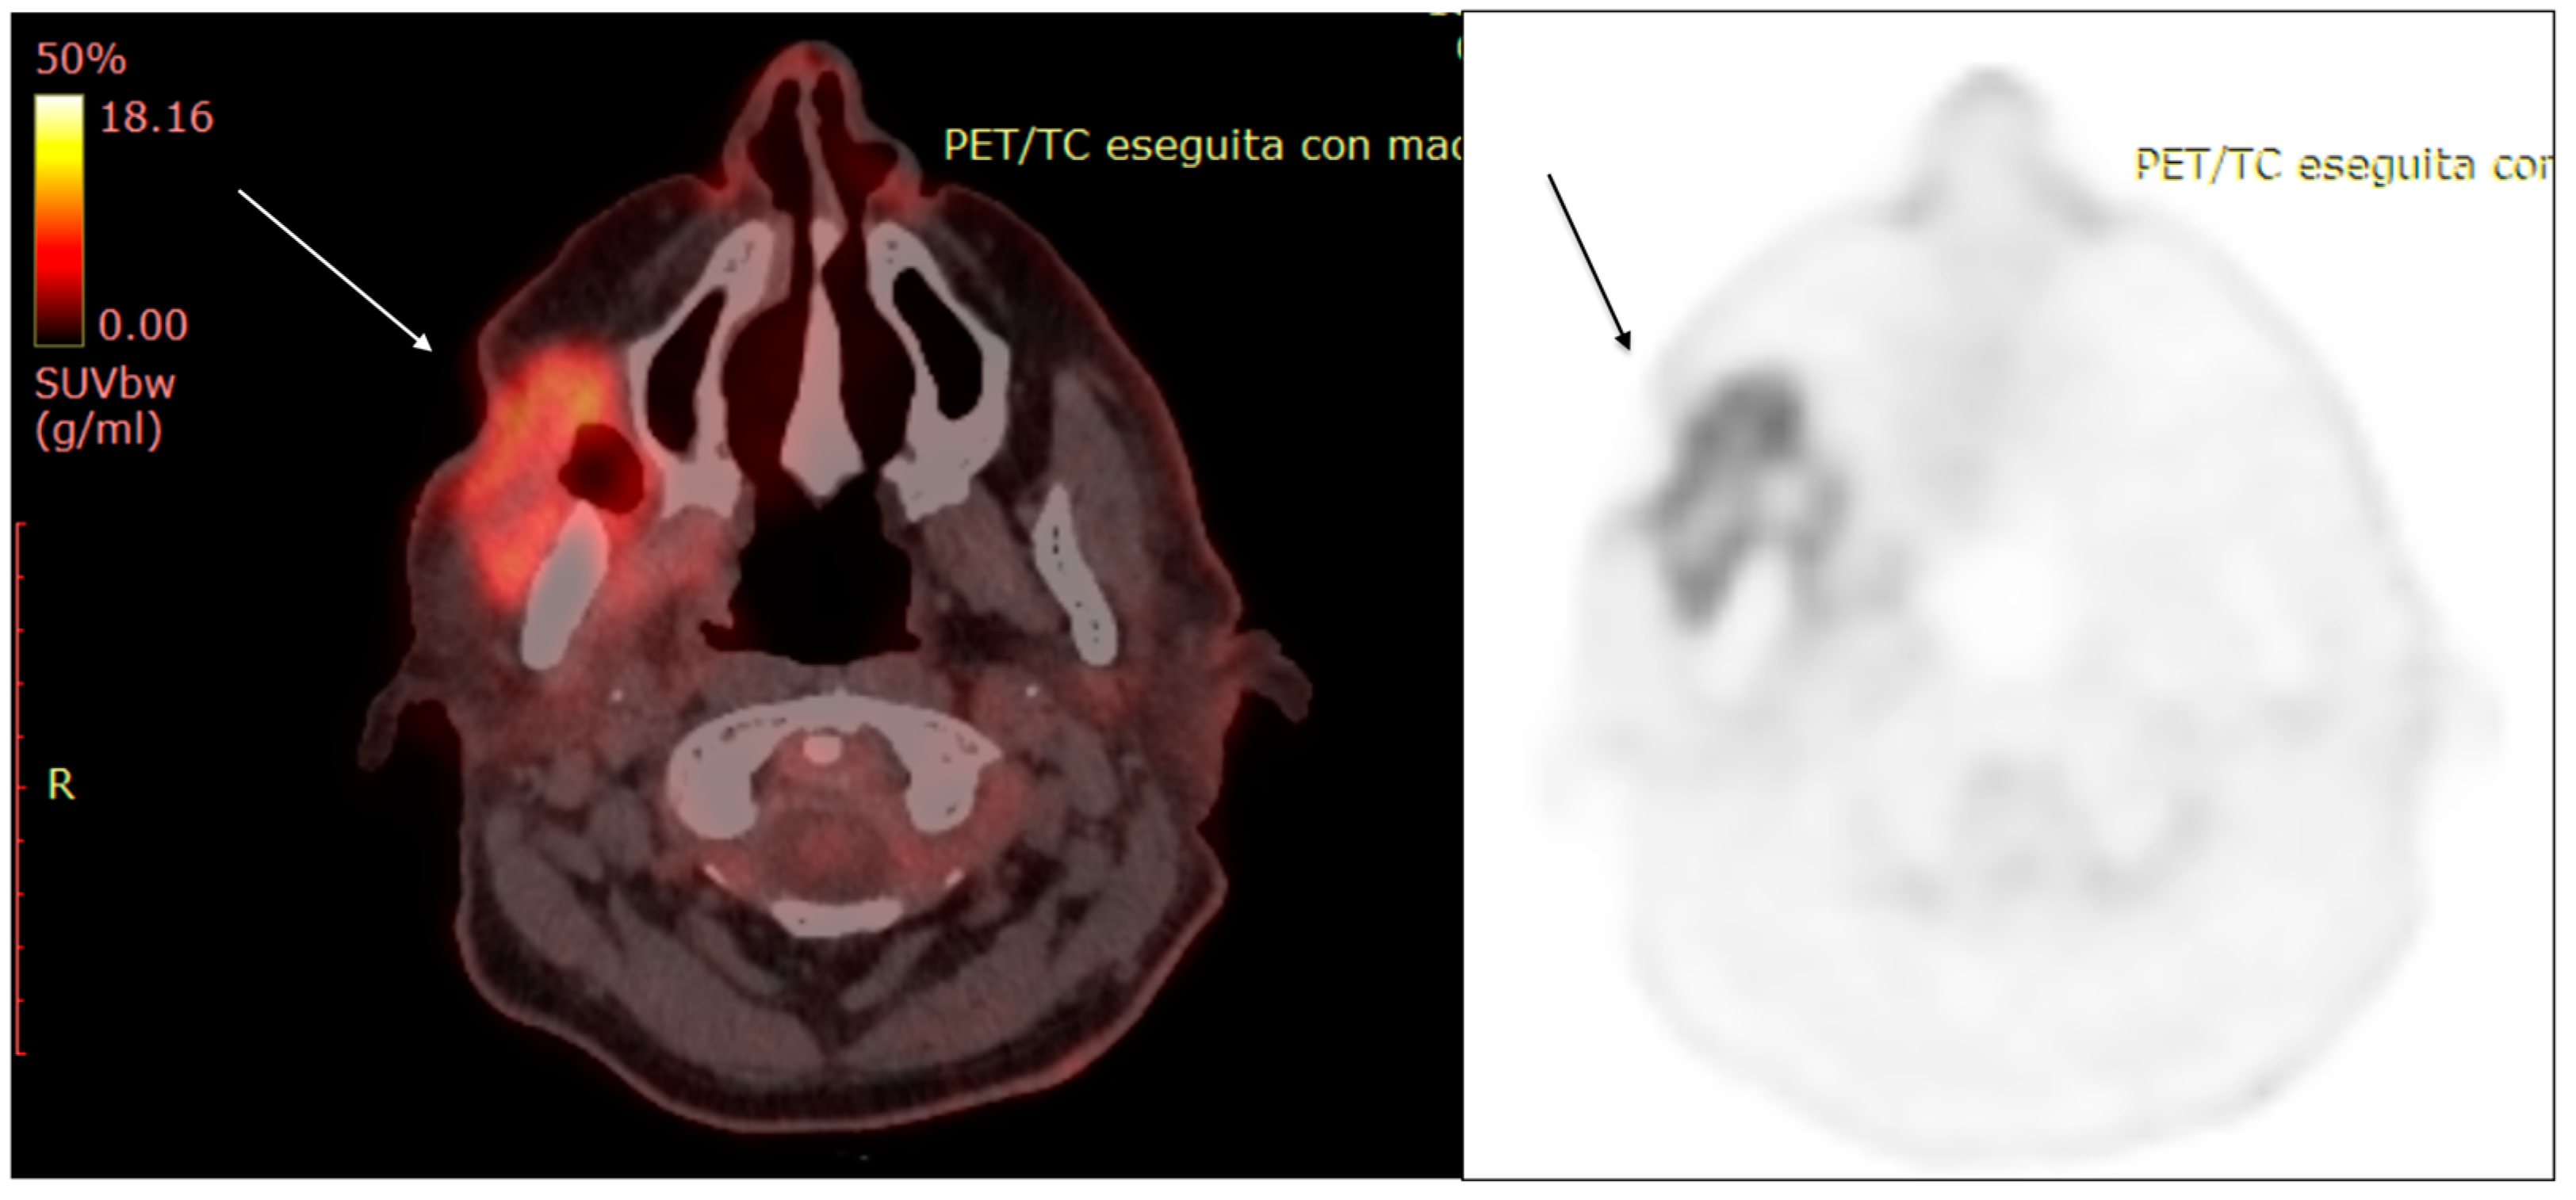

- Fosko, S.W.; Hu, W.; Cook, T.F.; Lowe, V.J. Positron Emission Tomography for Basal Cell Carcinoma of the Head and Neck. Arch. Dermatol. 2003, 139, 1141–1146. [Google Scholar] [CrossRef] [PubMed]

- Ruiz, E.S.; Karia, P.S.; Morgan, F.C.; Schmults, C.D. The positive impact of radiologic imaging on high-stage cutaneous squamous cell carcinoma management. J. Am. Acad. Dermatol. 2017, 76, 217–225. [Google Scholar] [CrossRef] [PubMed]

- Kawaguchi, M.; Kato, H.; Matsuyama, K.; Noda, Y.; Hyodo, F.; Matsuo, M. Prognostic value of 18F-FDG PET/CT and MRI features in patients with high-risk and very-high-risk cutaneous squamous cell carcinoma. Br. J. Radiol. 2022, 95, 20211003. [Google Scholar] [CrossRef]

- Juan, Y.-H.; Saboo, S.S.; Tirumani, S.H.; Khandelwal, A.; Shinagare, A.B.; Ramaiya, N.; Krajewski, K.M. Malignant Skin and Subcutaneous Neoplasms in Adults: Multimodality Imaging With CT, MRI, and 18F-FDG PET/CT. Am. J. Roentgenol. 2014, 202, W422–W438. [Google Scholar] [CrossRef]

- Mahajan, S.; Barker, C.A.; Mauguen, A.; Singh, B.; Pandit-Taskar, N. Restaging [18F] fludeoxyglucose positron emission tomography/computed tomography scan in recurrent cutaneous squamous cell carcinoma: Diagnostic performance and prognostic significance. J. Am. Acad. Dermatol. 2020, 82, 878–886. [Google Scholar] [CrossRef]

- Mahajan, S.; Barker, C.; Pandit-Taskar, N. FDG PET/CT in staging cutaneous squamous cell carcinoma. J. Nucl. Med. 2017, 58, 121. [Google Scholar]